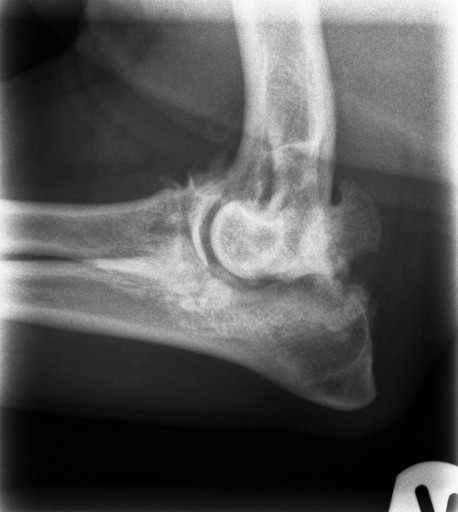

UAP